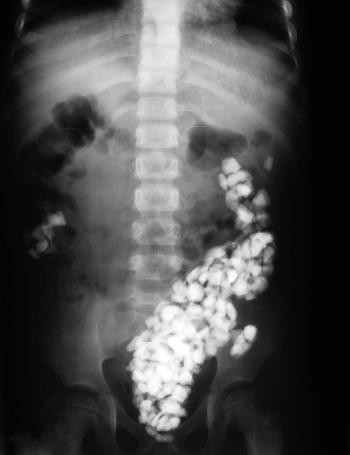

Patient swallows multiple foreign bodies.